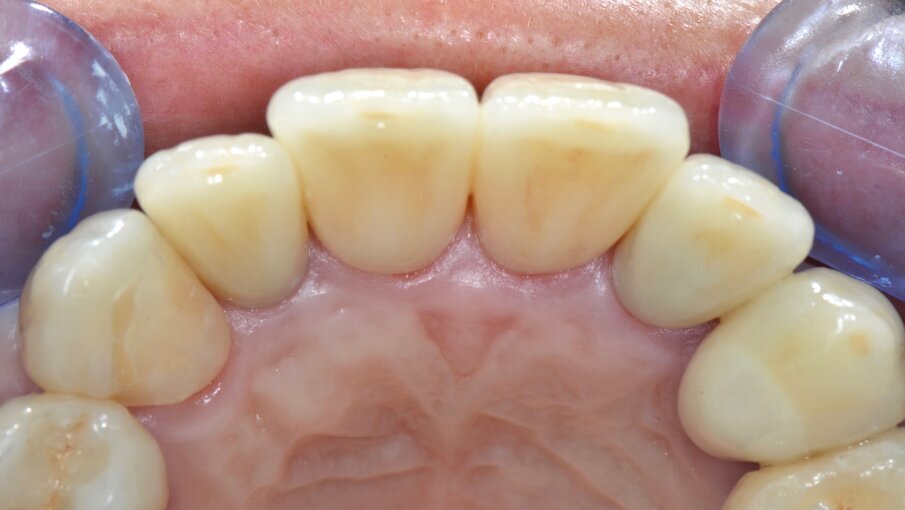

Valutiamo di aver raggiunto una buona simmetria delle parabole gengivali per cui si può procedere con la finalizzazione protesica (Fig. 20). I monconi sono stati preparati con una preparazione verticale per dare priorità alla robustezza dei monconi stessi nella zona cervicale (Figg. 21, 22).

Dal momento che si tratta di un caso estetico senza coinvolgimento parodontale la preparazione è stata molto delicata nei confronti dei tessuti con un posizionamento previsto delle corone definitive leggermente intrasulculare. Una buona conoscenza della fisiopatologia del parodonto unita ad una ottimale gestione degli aspetti protesici dimostra che con ogni tipo di finishing-line si possono ottenere risultati estetici soddisfacenti, ben sapendo peraltro che l’estetica dei manufatti protesici dipende soprattutto dalla bravura e dal senso artistico dei nostri odontotecnici.

Le impronte per il restauro definitivo vengono rilevate tramite polieteri con tecnica in un tempo a due fasi e cucchiai individuali e tecnica di retrazione gengivale con doppio filo.

Le corone definitive, come precedentemente descritto, vengono costruite con tecnologia CAD/CAM per una sottostruttura in zirconia di cui viene verificato l’adattamento e ricercata la precisione seguendo gli stessi criteri noti per una prova fusione di una struttura metallica (Figg. 23-29). Dopo la prova le strutture vengono inviate in laboratorio per la stratificazione della ceramica.